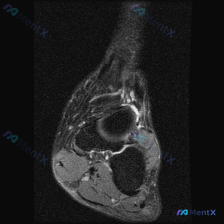

患者说踝关节有软组织积液感,但这张MRI居然没看到异常?

问题:患者主诉踝关节感觉有软组织积液,请读片判断

影像:踝关节MRI-脂肪抑制序列-轴位单张图像

这是踝关节远端水平的轴位扫描,先给大家整理一下观察结果:

- 骨骼:胫骨远端、腓骨远端骨髓信号正常,没有水肿、骨折线或骨质破坏

- 肌腱系统:腓骨长短肌腱、跟腱、胫骨后肌腱、趾长屈肌腱、踇长屈肌腱走行清晰,没有异常高信号,也没有看到腱鞘积液环绕

- 韧带:未见韧带连续性中断,也没有损伤后周围软组织水肿的高信号表现

- 关节腔与软组织:关节间隙没有异常高信号积液,周围软组织结构层次清晰,没有弥漫性水肿或异常占位